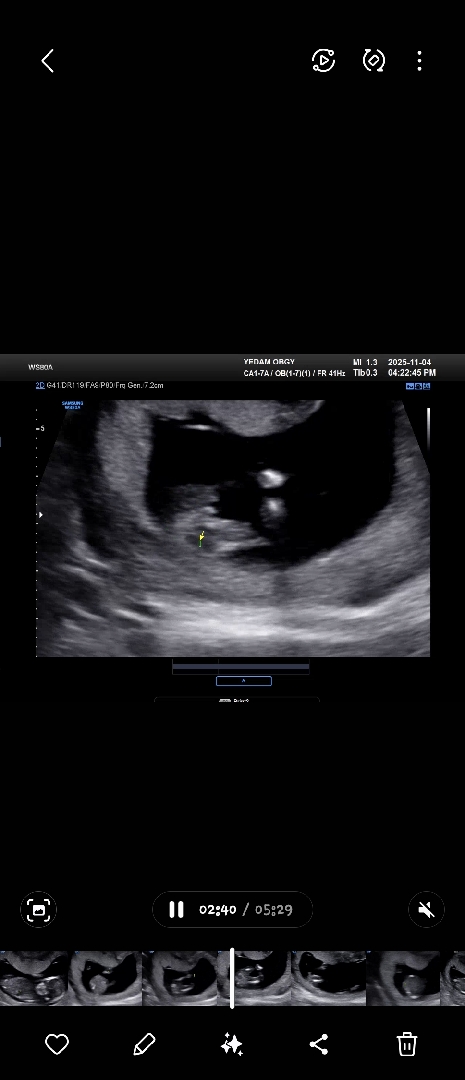

13주4일 성별부탁드려요♥︎

성별마구마구 투표해주세요